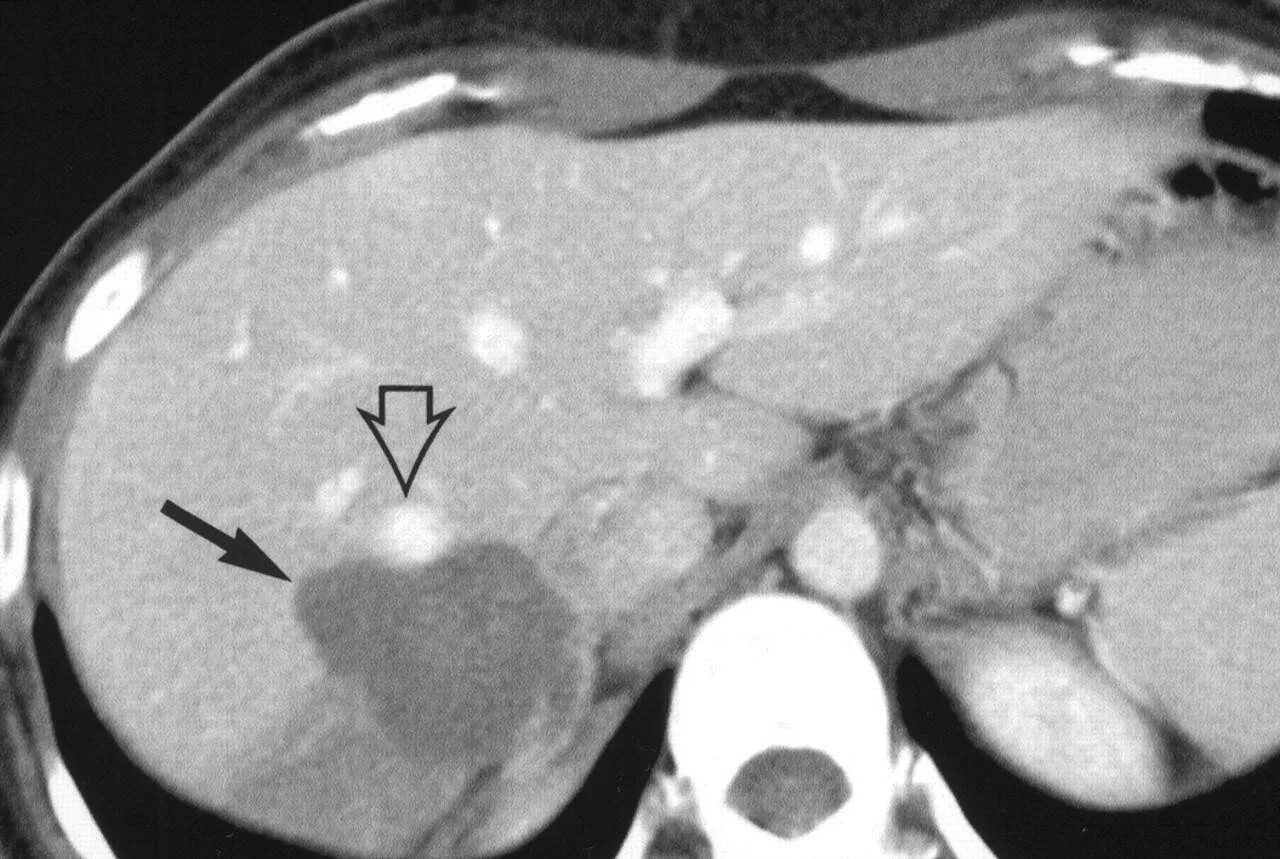

Народное лечение гемангиома печени